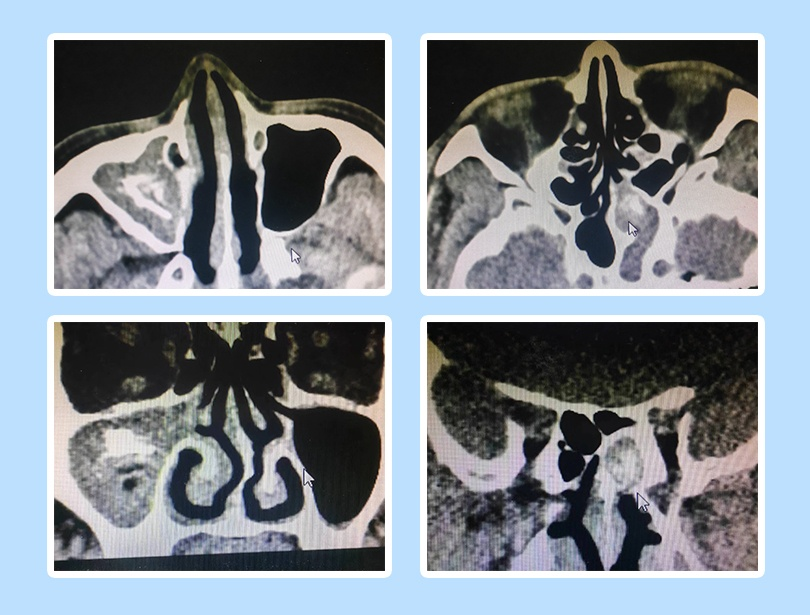

?4月10日,我院耳鼻喉科成功完成1例鼻內(nèi)鏡下真菌性鼻竇炎手術(shù),患者王先生(化名),因“鼻塞、流涕、頭痛”等癥狀來院就診,經(jīng)檢查,并結(jié)合病史癥狀及體征,初步診斷為真菌性鼻竇炎。

“食物放久了會發(fā)霉,甚至有時衣服在潮濕的環(huán)境放久了也會發(fā)霉,這種霉實際上就是生長的真菌。自然界中的真菌大約10萬種,其中可引起人類疾病者約數(shù)百種。”耳鼻喉科主任佟勇介紹,王先生感染的屬于非侵襲性真菌性鼻竇炎中的真菌球型。治療不及時,可導(dǎo)致病情加重,臨床癥狀有鼻黏膜充血、鼻塞、流涕、發(fā)熱、咳嗽、視力模糊、眼球腫脹等。佟主任談到,真菌性鼻竇炎很常見,從醫(yī)以來做過很多例這樣的手術(shù)。上頜竇真菌感染波及相鄰篩竇真菌感染的也見過,但一處病灶在右側(cè)上頜竇、另一處在左側(cè)蝶竇,兩處病灶分處不同鼻腔、相距甚遠,比較罕見。

根據(jù)王先生病情,佟主任決定為其實施鼻內(nèi)鏡下鼻竇開放手術(shù),清除鼻竇內(nèi)的真菌球。術(shù)中,在患者左側(cè)蝶竇、右側(cè)上頜竇均發(fā)現(xiàn)大量真菌團塊,清除后開放鼻竇,為患者重建鼻腔和鼻竇的通氣引流通道。手術(shù)在鼻內(nèi)鏡下完成,具有“微創(chuàng)、損傷較小、術(shù)野清晰、術(shù)后恢復(fù)快”等優(yōu)勢。